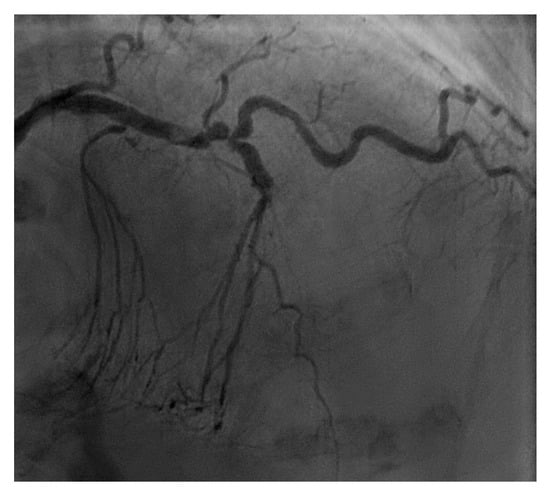

From a pure anatomical standpoint, bifurcation cases with planned kissing stents or kissing balloon angioplasty are not ideal for robotic PCI primarily because the system can only advance one catheter actively. However, bifurcations where provisional side-branch intervention is planned are reasonable choices for robotic PCI. Cases with excessive vessel tortuosity may be successfully performed robotically (Figure 3); however, extreme arterial angulation, or lesions that are severely eccentric or have dissected plaque morphology may require the use of tactile feedback that is not afforded by the robot and are not ideal (Figure 4). Although the advanced wire techniques required for anterograde wire escalation, dissection re-entry approaches, or retrograde approaches in chronic total occlusion intervention are not applicable robotically, we have used the robot to deliver and perform balloon angioplasty, stenting, and post-dilatation after first successfully manually crossing chronic total occlusions with a guidewire (Figure 5). Although the current generation system allows the operator to make fine adjustments in the guide catheter position, ostial lesions, particularly involving the RCA can be very challenging to perform robotically (Figure 6). Finally, cases that require the use of aspiration, atherectomy, filter wires, or certain imaging catheters (OCT and some IVUS), are not suitable for stand-alone robotic PCI.

Figure 3.

Example of a complex lesion involving the LAD in a patient with angina and severe tortuosity (A). Despite the tortuosity, the lesion was successfully wired, ballooned, and stented robotically (B). Post stent result shown in (C).